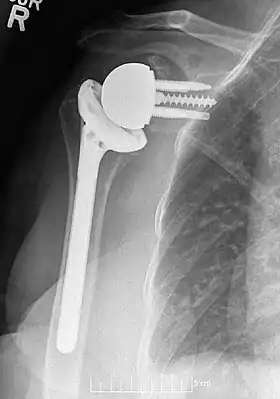

Plain film radiograph in anteroposterior (AP) view of a right shoulder status post reverse shoulder arthroplasty using a prosthesis with a lateralized center of rotation.

Modern reverse shoulder implants consist of multiple parts. On the scapula bone, there is a metallic baseplate that grows into the bone of the native glenoid, screws and/or pegs that hold this in place, and a round metallic “glenosphere” component that is mated to the baseplate via several different mechanisms. On the humerus bone, there is typically a concave polyethylene liner that articulates with the convex glenosphere and is attached to a humeral stem that grows into the native humerus or is cemented into place. Within this basic structure there are multiple different variations of implants, and to date there is no consensus on which design is superior, although several studies have demonstrated some benefits to certain combinations.[9][10][11] One such modern reverse shoulder implant system is the AltiVate Reverse.